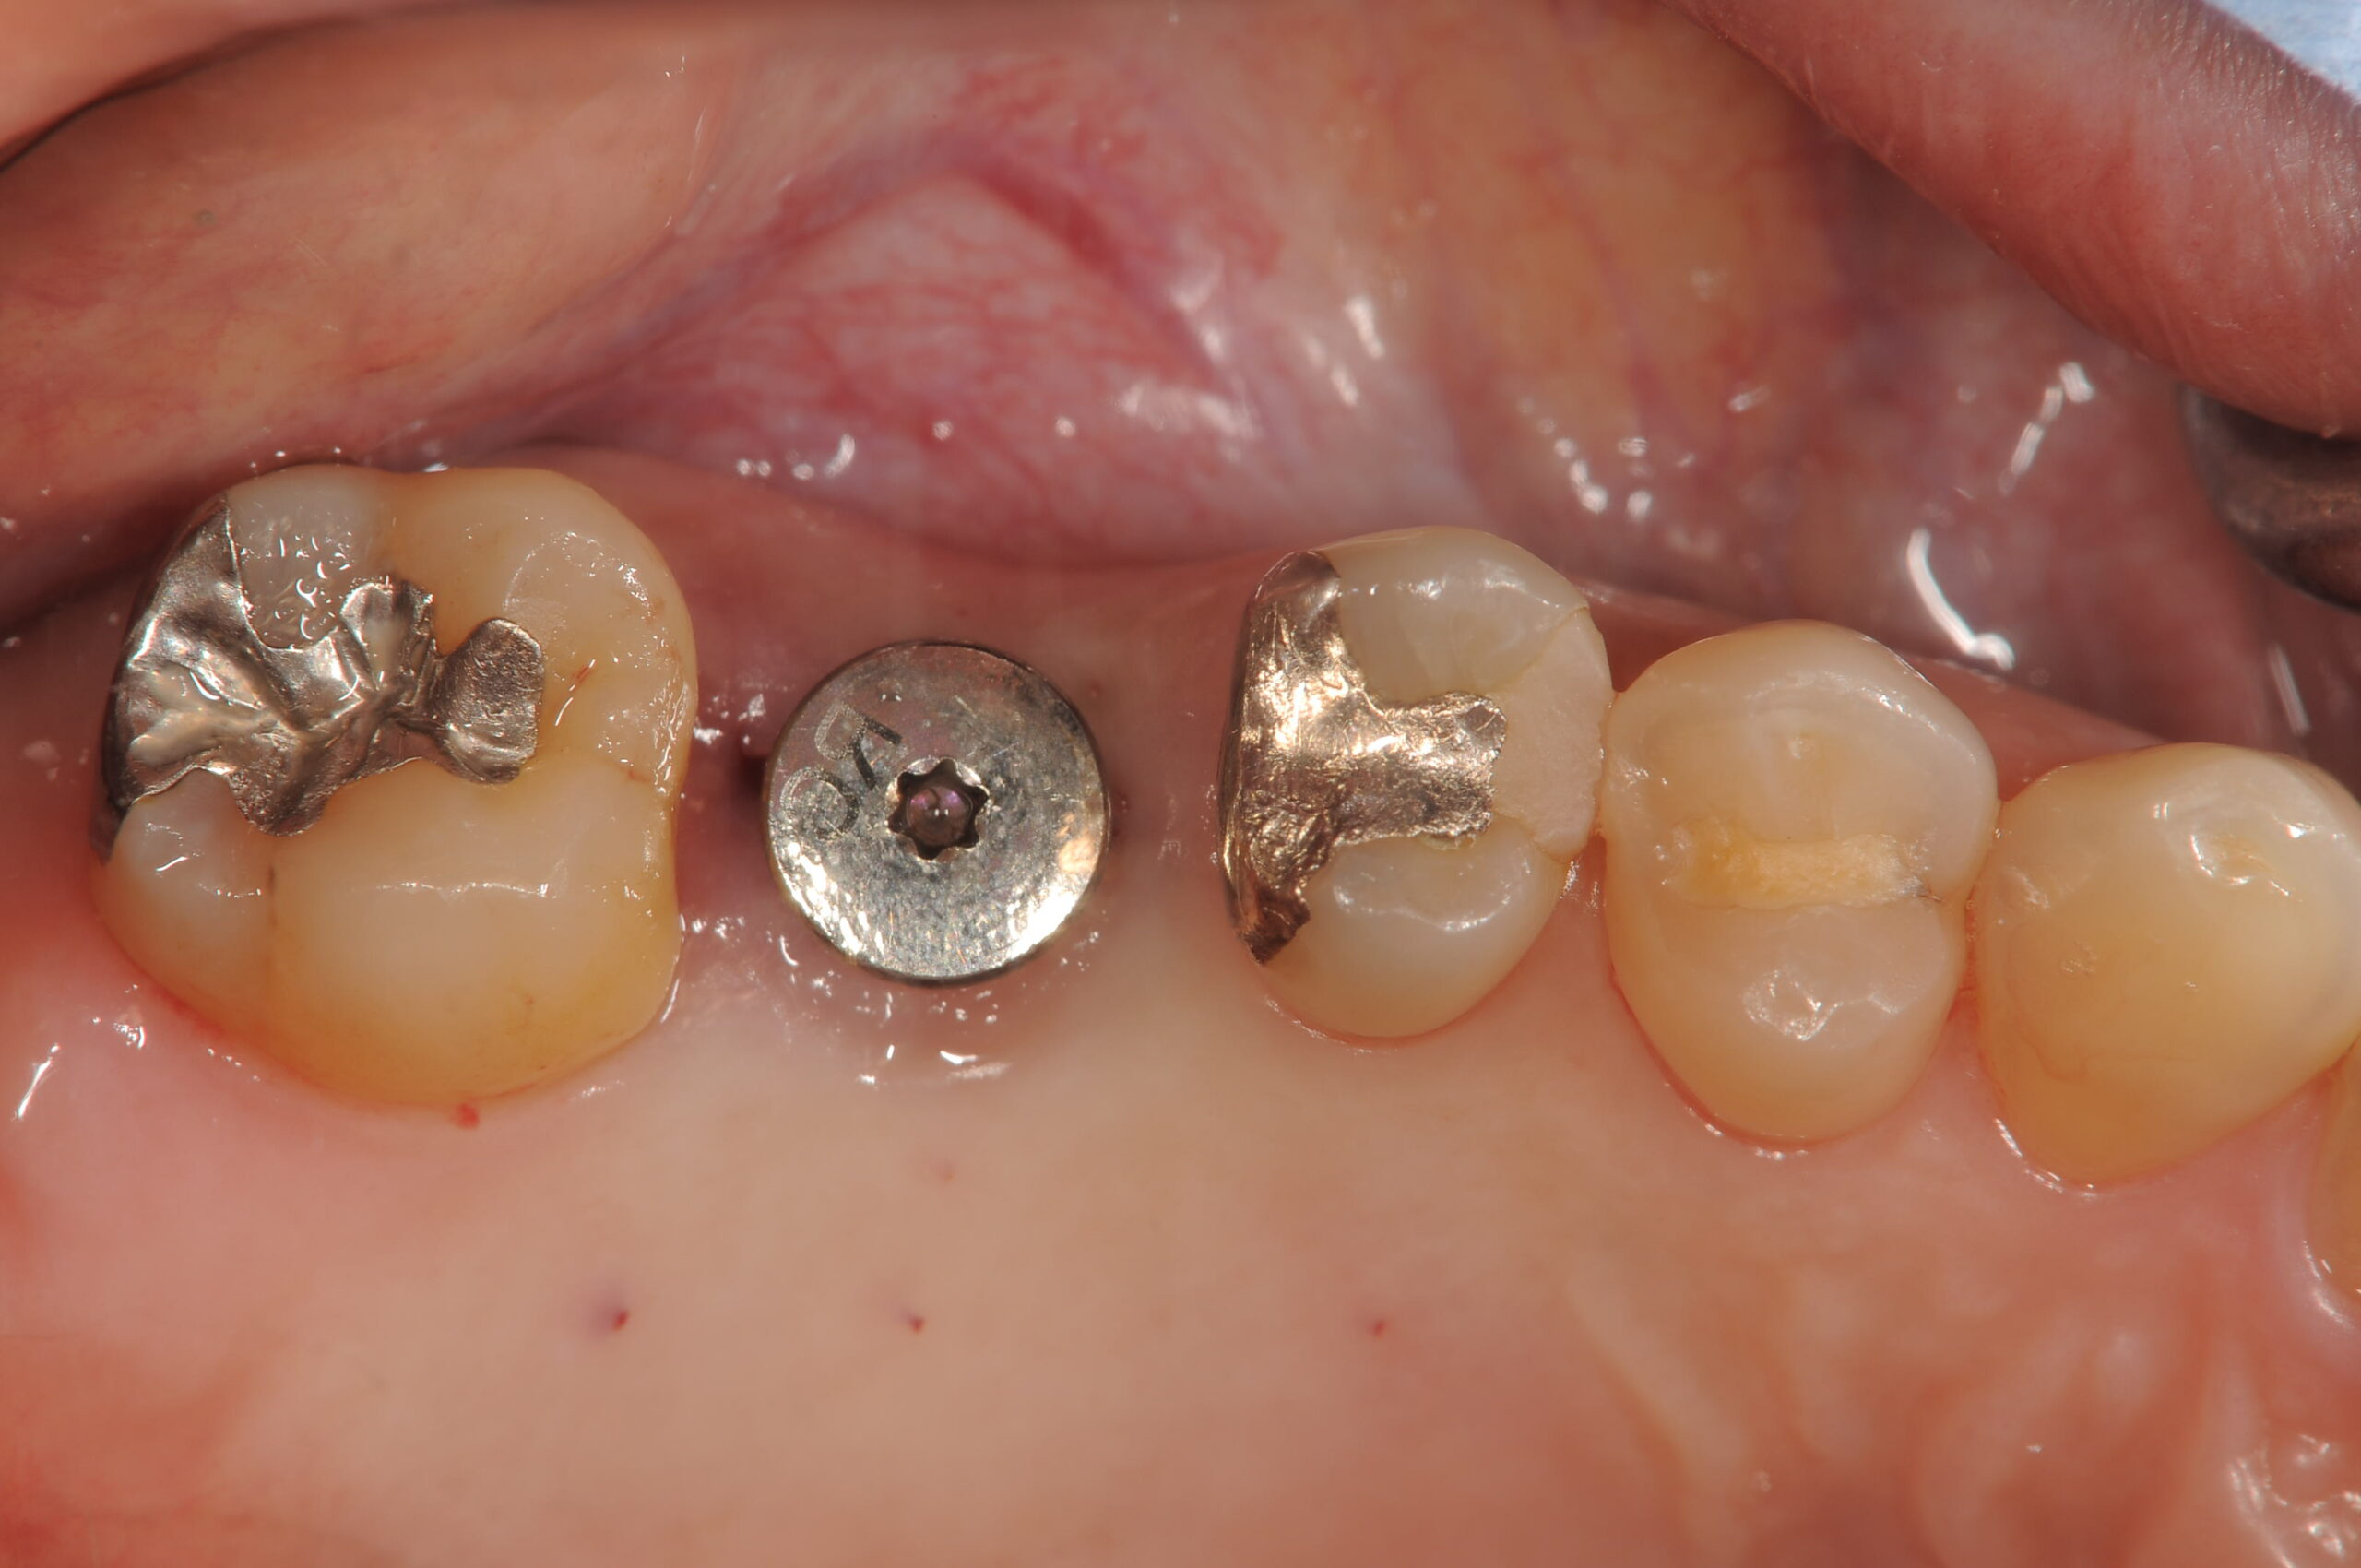

オペ直後の口腔内所見ですが、外科手術後とは思えません。